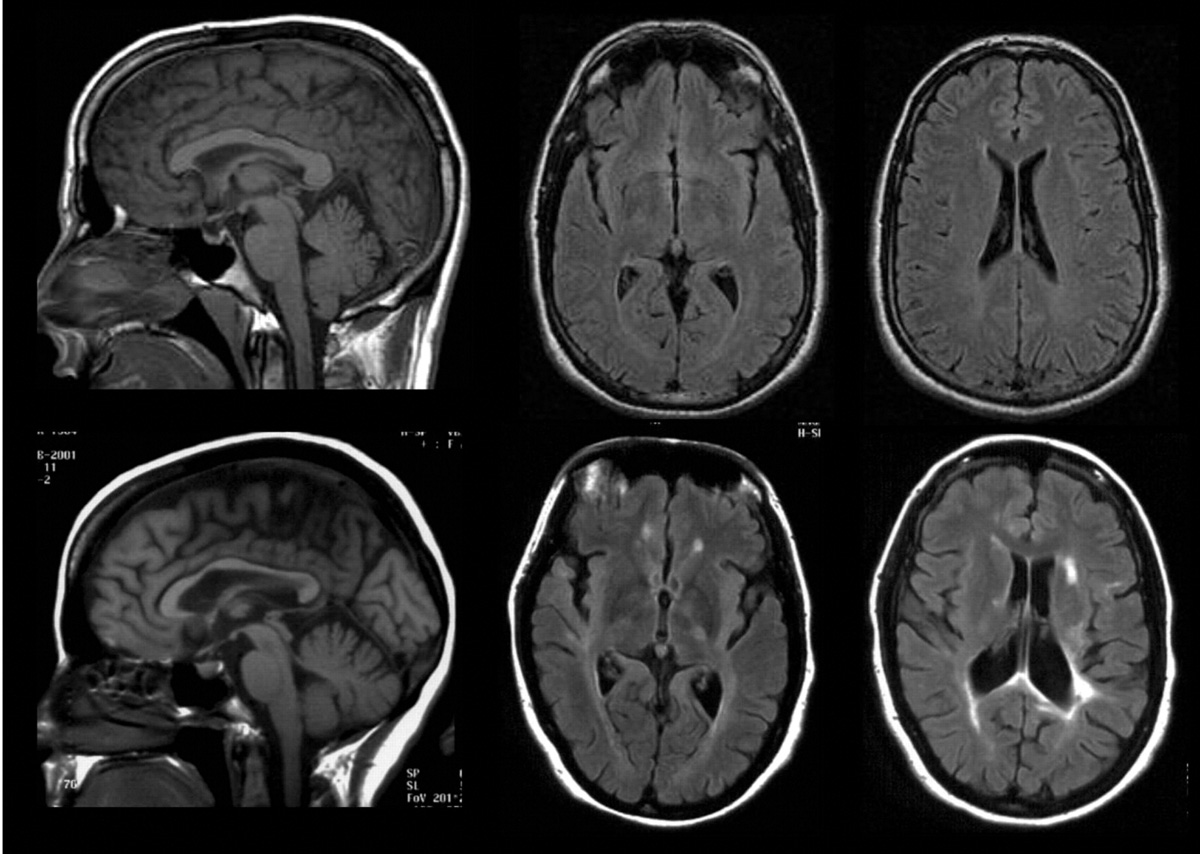

Кунио Накамуро и его коллеги из Монреальского неврологического института установили, что мозг человека уменьшается в течение дня, а на следующее утро его объем восстанавливается. Исследование основано на анализе почти 10.000 снимков магнитно-резонансной томографии мозга. Канадские ученые исследовали 3269 сканирований головного мозга в ходе испытаний с участием больных рассеянным склерозом, еще 6114 респондентов проекта страдали болезнью Альцгеймера. Что делает данное исследование крупнейшим в области неврологии.

Сравнивая снимки мозга одних и тех же испытуемых, но сделанные в разное время суток, неврологи обнаружили существенное увеличение объема мозга по утрам. У респондентов с рассеянным склерозом к вечеру мозг уменьшался на 0,18%, а у второй группы - на 0,44%. Для сравнения - примерно такая же степень сокращения объема мозга происходит у людей за год при развитии болезни Альцгеймера.